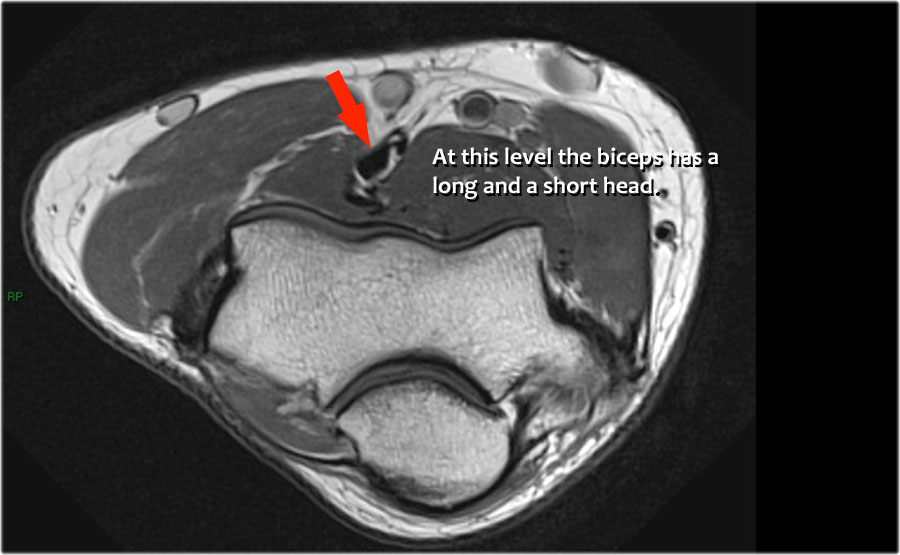

Cuộn qua các hình ảnh cắt ngang của gân cơ nhị đầu từ chỗ nối cơ-gân đến điểm bám tận trên lồi củ xương quay.

Bệnh lý của gân cơ nhị đầu đoạn xa rất giống với bệnh lý của gân Achilles.

Có thể gặp thoái hóa gân, rách một phần và rách hoàn toàn có hoặc không có sự co rút.